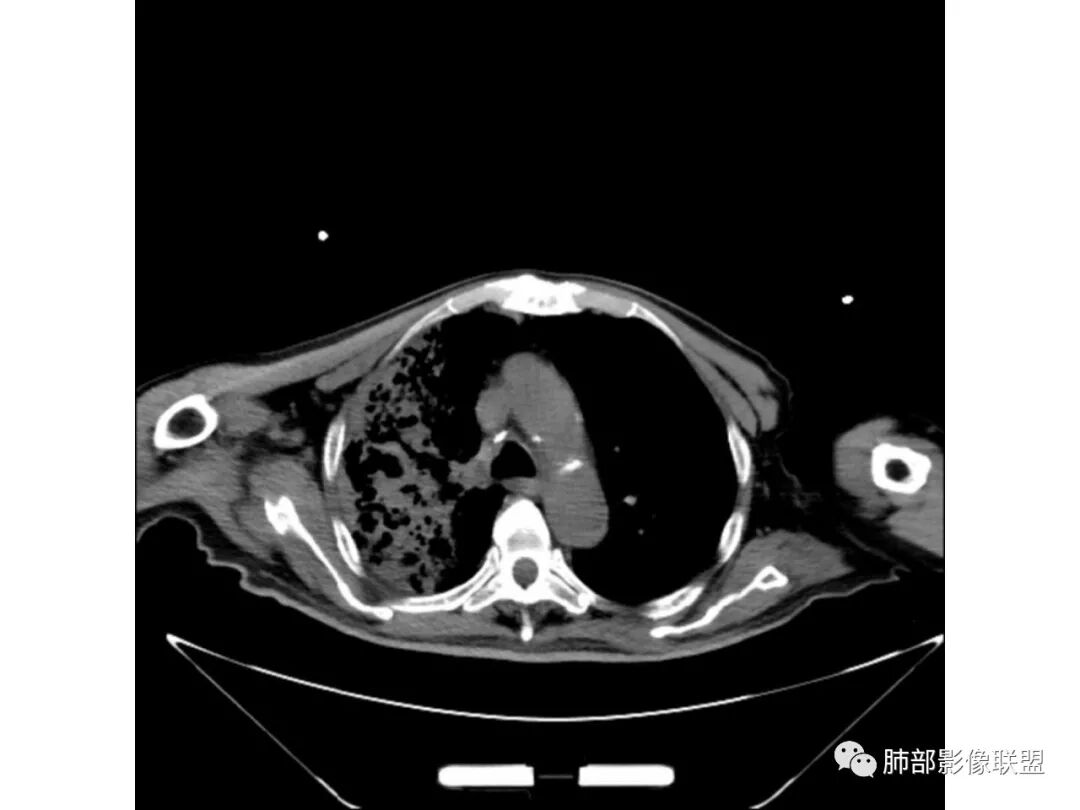

老年男性,糖尿病病史,咳嗽咳痰10余天入院。右上肺实变,见支气管充气征,部分支气管扩张,虫蚀样空洞,无壁空洞内壁光滑,实变病灶内见粘液成分,右上肺体积稍缩小,结核和肺炎性肺癌的鉴别,结核可能大,合并间质性肺病。

老年男性,右上肺大片实变,内见支气管充气征,支气管通畅,见多发蜂窝状改变,双肺肺气肿,双肺胸膜下间质性改变。结合病史,咳嗽,糖尿病史,考虑感染,结核可能。鉴别肺炎型肺癌,肺克;建议增强,支气管镜检查

老年男性,咳嗽、气喘十余天。2型糖尿病10年。胸部CT:右肺上叶实变影,见支气管充气征,部分支气管狭窄、虫蚀空洞,空洞内可见磨玻璃影,有囊变,双肺胸膜下磨玻璃影,肺气肿背景。综合考虑良性病变。结核、肺克可能性大。鉴别真菌及恶性。

病灶位于肺外周为主,支气管走行僵硬,考虑腺癌?鉴别间质病变并结核。

老年男性,有糖尿病病史,右侧胸廓塌陷,肺容积缩小,右肺上叶片状实变密度影及高密度影,边缘模糊,内可见支气管充气征及多发虫蚀样空洞,考虑结核可能大。肝脏只有一层,看上去正常

老年男性,糖尿病患者。右肺病变,病灶区多发树芽、管状透亮区,考虑为扩张支气管,说明为支气管源性病变。结核?真菌?肺癌?病灶区多发空洞,空洞内坏死不太彻底,树芽征跟增殖结节不明显,结核先不考虑。病灶区晕征不太明显,边界相对清楚,小叶间隔增厚~似呈结节状改变,支气管枯树枝征。最后,肺癌首先考虑,粘液腺癌?鉴别曲霉菌